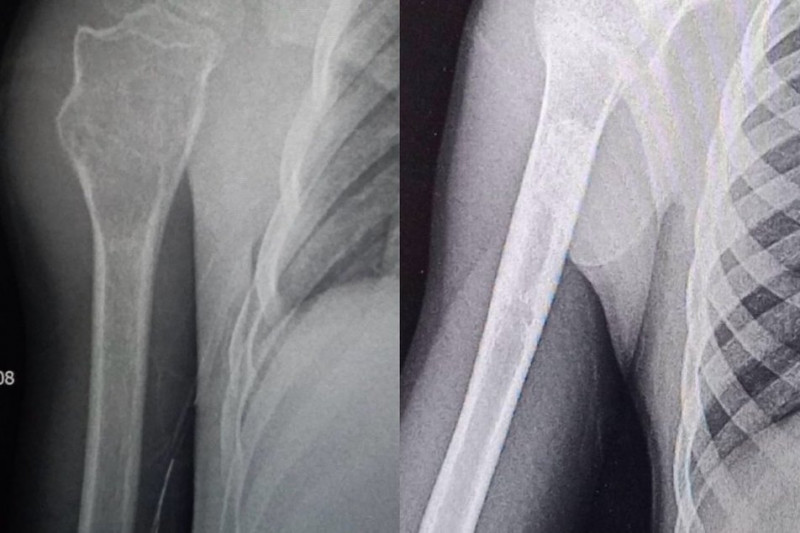

"Після проведення рентгенографії виявили значних розмірів кісту у проксимальному відділі плечової кістки — діагноз кісткова кіста. У цьому клінічному випадку спеціалісти ортопедо-травматологічного центру застосували метод пункційного лікування", — зазначили в публікації.

Кісткову кісту пролікували медики на Рівненщині. Facebook Рівненська обласна дитяча лікарня

У лікарні пояснили, що пацієнту тричі, з інтервалом у три місяці, виконували промивання кісти під загальним знечуленням та вводили у її порожнину спеціальний гормональний препарат.

"Метод дозволив уникнути великого оперативного втручання та забезпечив чудовий результат: рухи в плечовому суглобі повністю відновлені, дитина повернулася до активного життя", — пояснили в повідомленні.